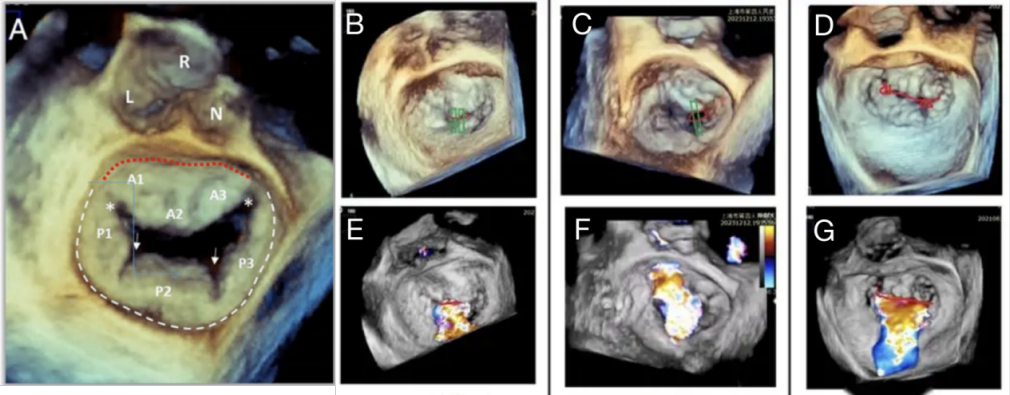

After an in-depth echocardiography review, the mitral regurgitant jets were further divided into central, marginal, or narrow subtypes, as described previously.21 Based on the 3D TEE image of the mitral valve from an overhead perspective (Figure 1), the central type was defined as a symmetric regurgitant jet in the middle of the valve (A2P2), commonly with unparalleled anterior leaflet remodeling in extreme annular dilation. The marginal MR type was reported in cases of regurgitant jets derived from inter-scallop indentations (P1-P2 or P2-P3) towards the anterior central scallop (A2), normally resulting from unparallel chordae tendineae elongation confronted with significant left cardiac remodeling. A narrow SMR subtype was reported when both subtypes were observed.